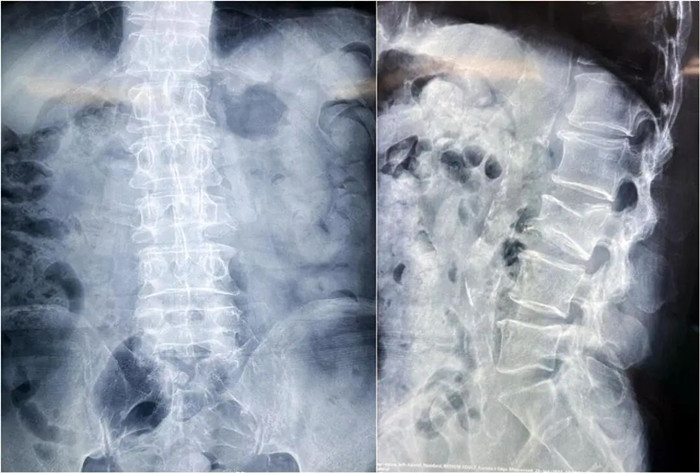

患者術前影像